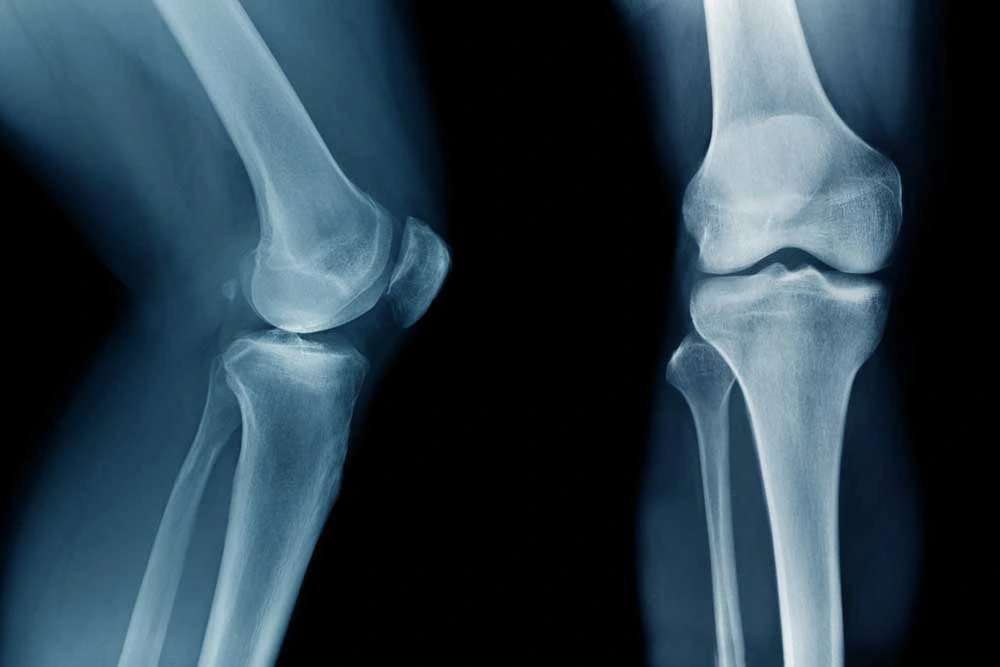

BEFORE THE SURGERY What tests and precautions are required before planning a knee replacement surgery? It is important to have good quality X-rays of the knee.

Read More +Components of a total knee replacement A total knee replacement prosthesis has four components: femoral component (made of metal) which is fixed to the cut.